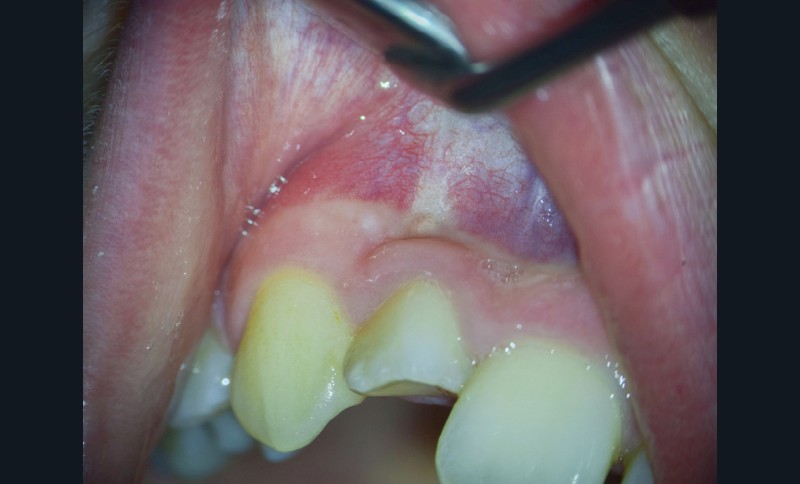

La patiente, âgée de 12 ans, s’est présentée à ma consultation avec une demande du chirurgien de réaliser le traitement endodontique de la 12 avant le curetage sous anesthésie générale. La radiographie périapicale préopératoire a mis en évidence une anatomie complexe. Les tests préopératoires ont montré un sondage parodontal sain, une percussion positive et un test au froid positif. La patiente présentait également une fistule vestibulaire active. Le Cone Beam a mis en évidence la présence d’une dens in dente et d’une lésion imposante ainsi qu’une palatoversion importante de la racine de la 12. La lésion est-elle responsable de ce mouvement dentaire ? (fig. 1, 2 et 3).

Lors du traitement endodontique, un suintement important étant encore présent à la fin de la seconde séance. J’ai pris la décision d’irriguer la crypte osseuse et sa lésion à travers la fistule à l’aide d’iso-bétadine délivrée par une aiguille stérile. C’est par empirisme que je réalise cette manœuvre ayant déjà montré à chaque reprise des résultats cliniques positifs. C’est l’équivalent d’une décompression sans tous les désavantages de cette dernière (fig. 4 et 5).